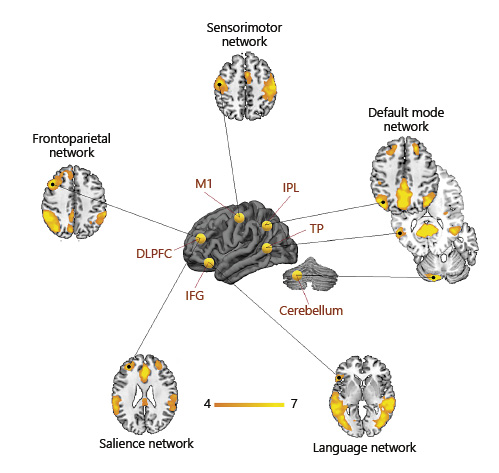

In the past 10 years, resting-state functional MRI (rs-fMRI) identified neural networks associated with specific cognitive and motor-sensory functions, and the neurodegenerative disorders associated with a dysfunction of these networks (Fig. 1). Studies suggest that memory is sustained by two networks, the default mode network (DMN) and the limbic network [15]. Neocortical networks such as the frontoparietal (FPN), visual, and language networks underlie executive, visuospatial, and language abilities, respectively [16]. Moreover, the so-called salience network (SN) is involved in social behavior, emotion regulation, and self-awareness [17].

Neural networks associated with specific cognitive and sensorimotor functions and the associated neurodegenerative disorders. Maps were extracted through independent component analysis from a sample of 20 healthy subjects.

Neural networks associated with specific cognitive and sensorimotor functions and the associated neurodegenerative disorders. Maps were extracted through independent component analysis from a sample of 20 healthy subjects.

To date, several studies have combined NIBS with rs-fMRI in young healthy subjects to investigate the modulatory effects of NIBS on brain networks (Table 1). Overall, these studies consistently reported that NIBS alters connectivity in the target brain region (local effect) but also in remote regions interconnected within the stimulated area (distal effect). These studies, reviewed below, are classified according to the target of stimulation (Fig. 2).

Common targets of NIBS reported in the literature (yellow spheres on 3D brain) are major nodes of large-scale functional networks. Each target can be used as a seed to derive functionally related (i.e., synchronous) regions of the brain. Stimulation of specific brain regions results in both local and distal functional connectivity modulation. Orange-yellow colors on axial slices represent the intrinsic functional connectivity degree (z score) of the major large-scale networks, extracted through independent component analysis from a sample of 20 healthy subjects.

Common targets of NIBS reported in the literature (yellow spheres on 3D brain) are major nodes of large-scale functional networks. Each target can be used as a seed to derive functionally related (i.e., synchronous) regions of the brain. Stimulation of specific brain regions results in both local and distal functional connectivity modulation. Orange-yellow colors on axial slices represent the intrinsic functional connectivity degree (z score) of the major large-scale networks, extracted through independent component analysis from a sample of 20 healthy subjects.